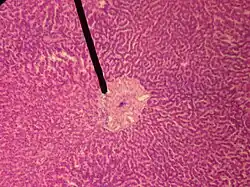

A single lobule of the liver of a pig. X 60. (Central vein not labeled, though region is visible. Central vein would be a single vein at the center of the lobule.)

In microanatomy, the central veins of liver (or central venules)[1] are veins found at the center of hepatic lobules (one vein at each lobule center).

They receive the blood mixed in the liver sinusoids and return it to circulation via the hepatic veins.[2]

The circulation of venous blood is: portal vein (which is formed by the joining of the superior mesenteric vein with the splenic vein) drains into the sinusoids of the liver, these all drain into the central veins of liver which drain into the hepatic vein to be returned to IVC.